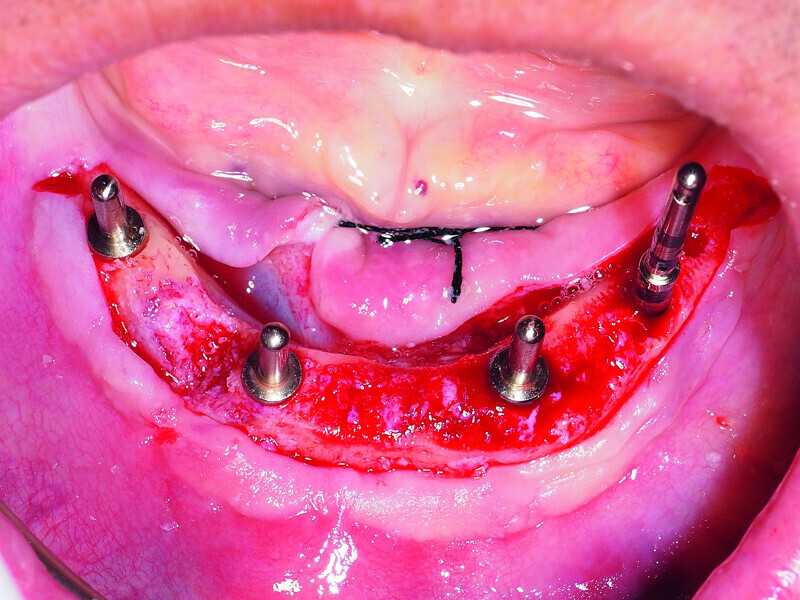

Fig. 2: Placement of four GC Aadva implants in the interforaminal region.